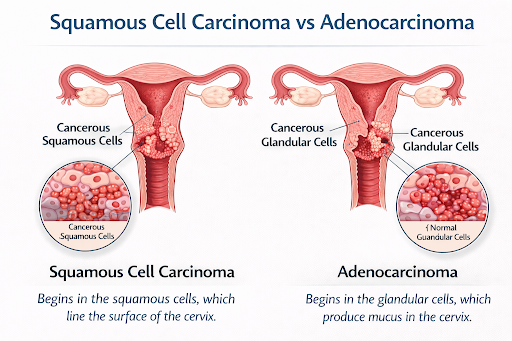

Main Types of Cervical Cancer

● Squamous Cell Carcinoma: Starts in the outer cervix (exocervix); most common type.

● Adenocarcinoma: Starts in glandular cells of the inner cervix (endocervix); less common but increasingly seen.

Main Types of Cervical Cancer

● Squamous Cell Carcinoma: Starts in the outer cervix (exocervix); most common type.

● Adenocarcinoma: Starts in glandular cells of the inner cervix (endocervix); less common but increasingly seen.